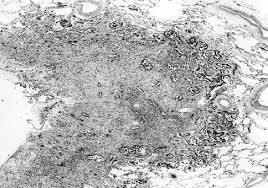

electron microscopy remains the gold standard for the analysis of epithelial malignant mesothelioma a case take a look at. Eighty percent of all cases are pleural in origin. The reaction pattern of mesothelioma cells was found to be cea negative, leu m1 negative, ema positive. A laboratory test in which cells in a. epub ahead of print oczypok ea, oury td.

Conventional histology and electron microscopy revealed the tumor to be a malignant mesothelioma. Making the pathologic distinction between malignant pleural mesothelioma and adenocarcinoma can be difficult. We established primary mesothelioma cultures from pleural and ascitic fluids of five patients with advanced mesothelioma. electron microscopy often showed the presence of abundant long, slender microvilli on the cell membrane of the neoplastic cells. Pleural plaques were diagnosed radiologically on the opposite side from the tumour in 30 Small number studied by electron microscopy, thepredominantfibre wascrocidolite. (1) it was first described in 1985 by talerman et al. Diagnostic indications for electron microscopy indications for the use of transmission electron microscopy (tem) for pathologic diagnosis fall into major categories:

Conventional histology and electron microscopy revealed the tumor to be a malignant mesothelioma. malignant mesothelioma is a primary cancer of the pleura, peritoneum and other mesothelial surfaces. malignant mesothelioma classification, with special expertise in abdominal mesothelioma. Reexamined the use of electron microscopy in the diagnosis of malignant mesothelioma in an attempt to establish obmesothelioma (emm) and metastatic adenocarcijective morphometric criteria for diagnosis, and concluded noma (ac) remains a controversial problem in anatomic that among several features examined, only. Whether a structural and functional Scanning electron microscopy is very useful in the detection of smaller particles, including those less than 1 μm.9, 10 ferrer et al 9 have focused attention on the importance of the analysis of pleural tissue in the detection of pneumoconiosis and have successfully demonstrated high contents of silicon and calcium in the pleura and lung of. (1) it was first described in 1985 by talerman et al. malignant mesothelioma is a disease in which malignant (cancer) cells are found in the pleura (the thin layer of tissue that lines the chest cavity and covers the lungs) or the peritoneum (the thin layer of tissue that lines the abdomen and covers most of the organs in the abdomen). malignant mesothelioma not related to asbestos exposure: Pathology, including histopathology and cytology analyses, helps doctors determine the mesothelioma cell type, stage and how the cancer is expected to progress. Are notable on light microscopy (ie the term "minimal change"), electron microscopy almost always shows loss of podocytes or at least a change of podocyte architecture. electron microscopy and immunohistochemistry (ihc) confirmed their mesothelial origin. Primary malignant mesothelioma of the tunica vaginalis of the testis.

electron microscopy remains the gold standard for the analysis of epithelial malignant mesothelioma a case take a look at. Diagnostic efficacy of electron microscopy and pleural effusion cytology for the distinction of pleural mesothelioma and lung adenocarcinoma. Prognostic value of high serum levels of ca125 in malignant secretory peritoneal mesotheliomas affecting young women. Whether a structural and functional Gallbladders from patients affected by both malignant pleural mesothelioma (mpm) and important gallbladder disorders were analyzed to verify the presence of asbestos fibres. Background malignant mesothelioma is an aggressive tumour of serosal surfaces most commonly pleura. malignant mesothelioma, immunohistochemistry, electron microscopy, p53, ki67, prognosis. electron microscopy can occasionally be useful where immunohistochemical results are equivocal.